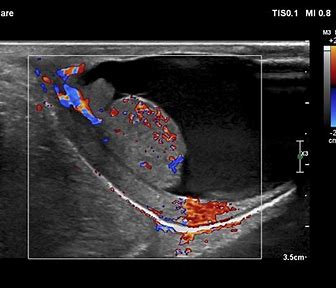

A testicular ultrasound is a non-invasive procedure that uses sound waves to create images of the testicles and surrounding structures in the scrotum. It is used to evaluate testicular masses, pain, swelling, or trauma.